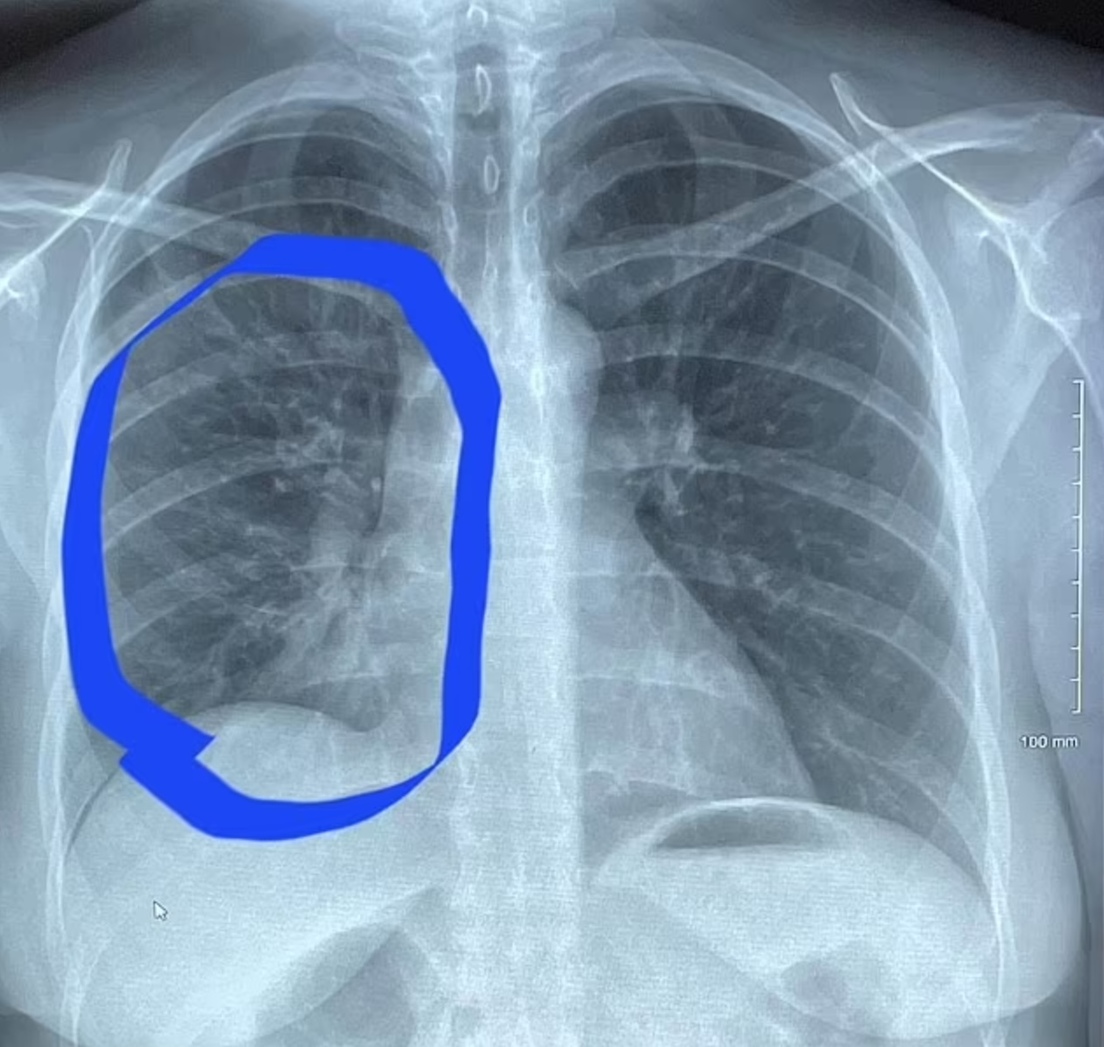

Roth comenzó el hábito de vapear hace cuatro años para lidiar con el estrés del bloqueo pandémico y pronto empezó a fumar "a cada hora del día". Las radiografías revelaron que sus pulmones se parecían a los de alguien de unos 80 años o que hubiera fumado por lo menos desde hace una década.